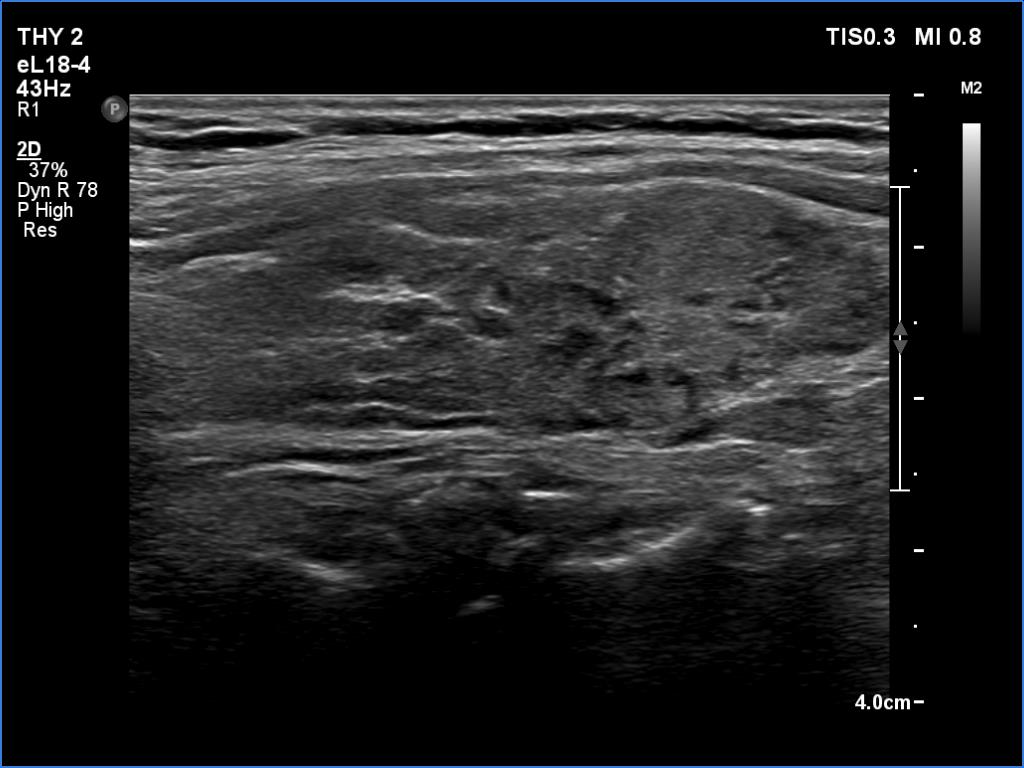

Lymphocytic thyroiditis - case 751

Right lobe

Focal form of lymphocytic thyroiditis is presented. The thyroid has numerous discrete, hypoechoic lesions which correspond to more active foci of thyroiditis. The interpretation of this pattern should not cause concern - these areas are not pathological nodules. The discrete lesions have non-regular, partly clearly lobulated or spiculated margins.